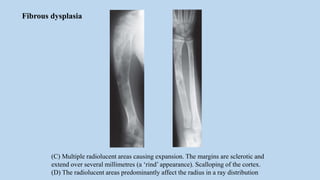

(C) Multiple radiolucent areas causing expansion. The margins are sclerotic and

extend over several millimetres (a ‘rind’ appearance). Scalloping of the cortex.

(D) The radiolucent areas predominantly affect the radius in a ray distribution